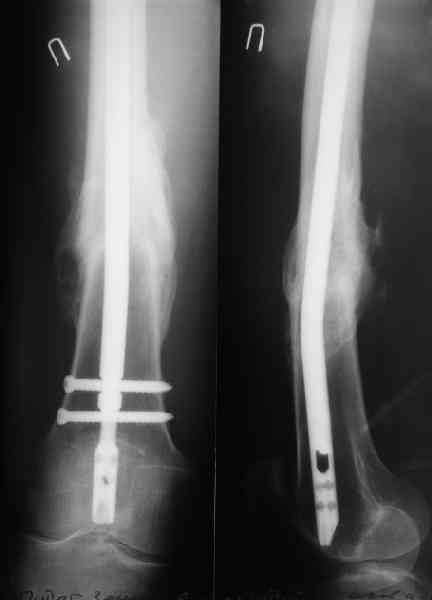

Пациенту М., 30-ти лет, 1,5 года назад в одной из московских больниц был выполнен остеосинтез бедренной кости штифтом UFN (диаметр штифта 9 мм).

К нам больной поступил с признаками ложного сустава бедренной кости, перелома

штифта и дистального блокирующего винта (images 1,2,3).

27 марта выполнено удаление блокирующих винтов (сломанный винт пришлось высверливать цапфен-бором), сломанного штифта (дистальный фрагмент удален через канал, образованный разверткой из коленного сустава - image 4),

рассверливание костно-мозгового канала, реостеосинтез штифтом UFN (при проведении штифта в дистальном отломке мы использовали поляризующий винт, диаметр штифта 10 мм). После операции в связи гемартрозом дважды (на 1 и 3 сутки) выполняли пункцию коленного сустава. Сейчас признаков скопления жидкости в полости сустава нет. Послеоперационные рентгенограммы - images 5, 6, 7.